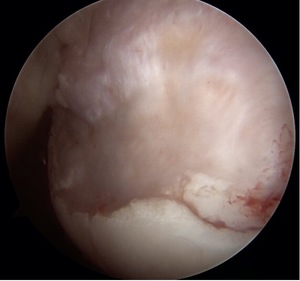

To combat these problems, I now use more anchors and mattress suture patterns. I often plicate the posterior inferior capsule, even when the tear doesn’t extend around the back. I have also learned, after training, how to execute a well-done open capsule shift and a Latarjet procedure. Although it has been close to 20 years since Eugene Wolf coined “Hill Sachs Remplissage”, this procedure has become increasingly popular as evidenced by the histogram spike in pub med publications using the word remplissage.(Image 2,3)

With this remplissage interest, we need to shed clarity on the best way to perform remplissage; do the anchors go at the articular margin of the defect, or more centered? Should we use one, or two (or more) anchors? Do we need to see the subacromial space? Is there an optimal position to limit the loss of external rotation?

Remplissage also results in greater loss of range of motion compared to a Latarjet. This is a troublesome result for overhead athletes, and raises concern for long term over constraint and arthrosis. McDonald and Yang’s data also both suggest the highest failure rates observed with remplissage are young, males, collision athletes and revision surgery.(Image 4) This reality must also play into an algorithm.